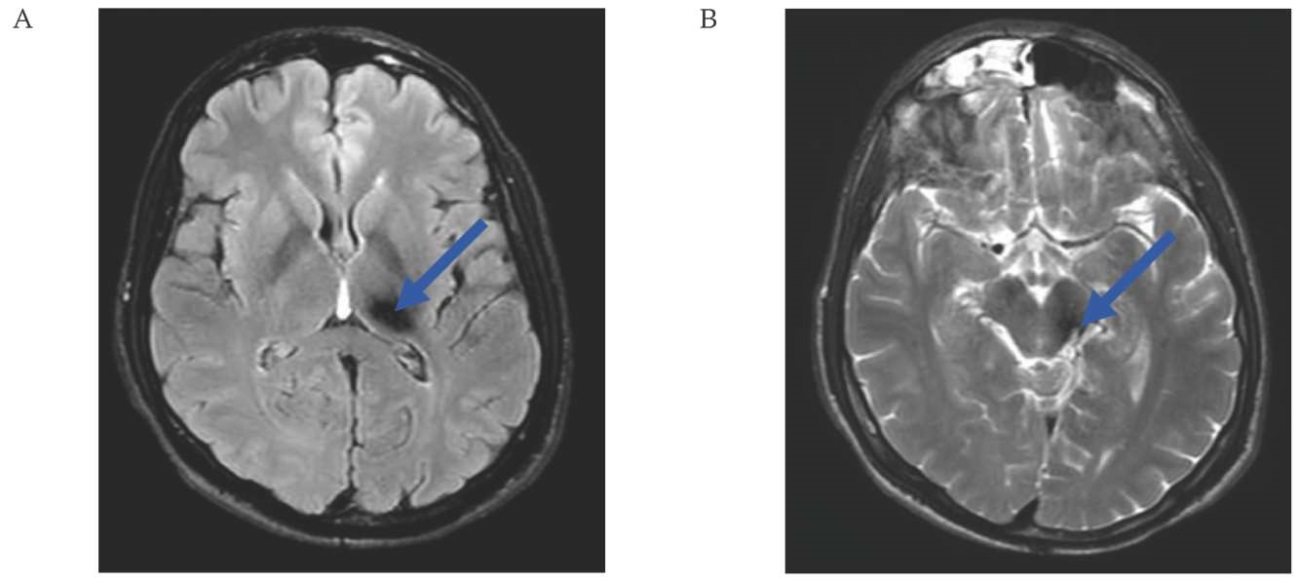

По данным контрольной МРТ головного мозга от 18.02.2025: состояние после удаления каверномы. МР-признаки постоперационных глиозных изменений. Остаточной каверномы и повторного кровоизлияния не выявлено (рис. 5A, B).

РИС. 5. Магнитно-резонансная томография головного мозга пациента 38 лет через 9 месяцев после удаления кавернозной мальформации в дорсальной части левой ножки среднего мозга (18.02.2025).

А, В. Аксиальные срезы: постоперационные глиозные изменения (стрелки).